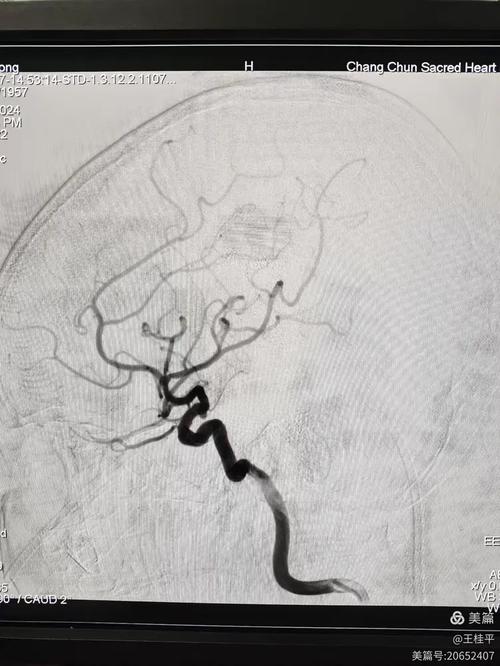

脑动脉血管瘤术 脑梗

(图片来源网络,侵删)